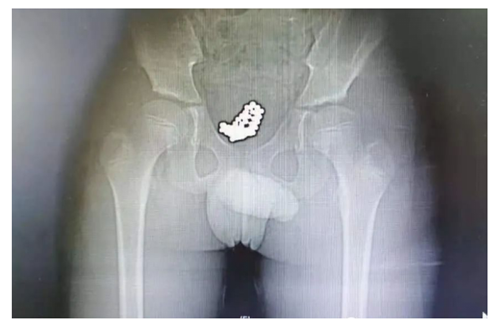

男孩名叫央奇(化名),今年10岁。因尿痛、血尿1天,于7月9日上午10点,由父母带领来到香港马会app看急诊。医生询问病情时,发现小奇全程都低着头,好像试图躲避医生和家长的眼神,只说自己头天下午去游了泳,其他一概支支吾吾、避而不答。随后,医生给他拍了一个CT,一拿到片子就大致猜到是怎么回事了。“从片子可以清晰看到,他的膀胱里充满了一颗颗小珠子,直径大约5毫米 ,估计是不久前塞进去的!”泌尿外科副主任医师刘明分析。

患者的CT片

手术过程中,医生经尿道将输尿管镜推送至膀胱内,镜下见吸附到一起的磁珠体,形似“石榴”,磁珠之间吸附力强大,镜下无法一一分开,只能行膀胱切开异物取出术。术中将吸附在一起的磁珠体完整取出体外,经检查,共计74颗,手术过程顺利,术后恢复良好。

患者膀胱内取出的磁珠